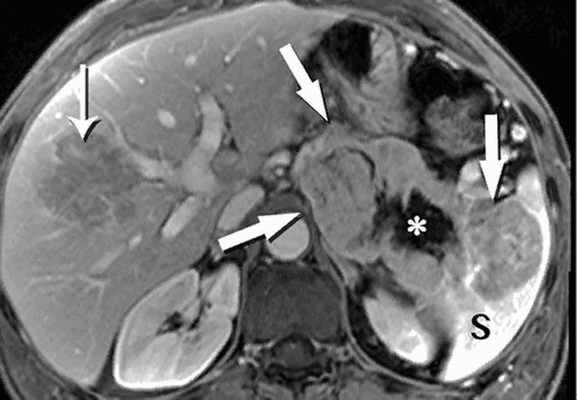

МРТ: нейроэндокринная опухоль поджелудочной железы (толстые стрелки), расплавление хвоста и инвазивный рост в селезенку (S). Звездочка показывает зону некроза, тонкая стрелка - большой метастаз в печени

МРТ: А - резкое изменение просвета панкреатического протока - косвенный признак опухоли тела поджелудочной железы небольшого размера. В - снимок, сделанный в артериальную фазу МР-ангиографии, при увеличении демонстрирует новообразование, вызывающее обструкцию протока (толстая стрелка), тонкая - печеночная артерия, короткая - верхняя брыжеечная артерия